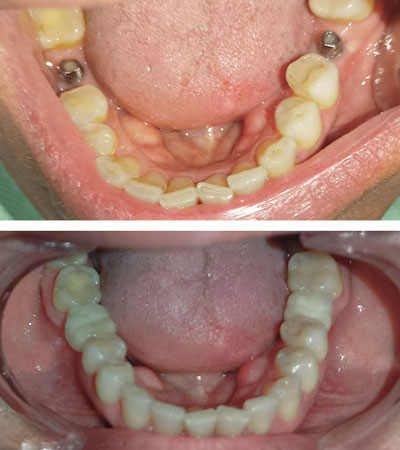

CASOS CLÍNICOS